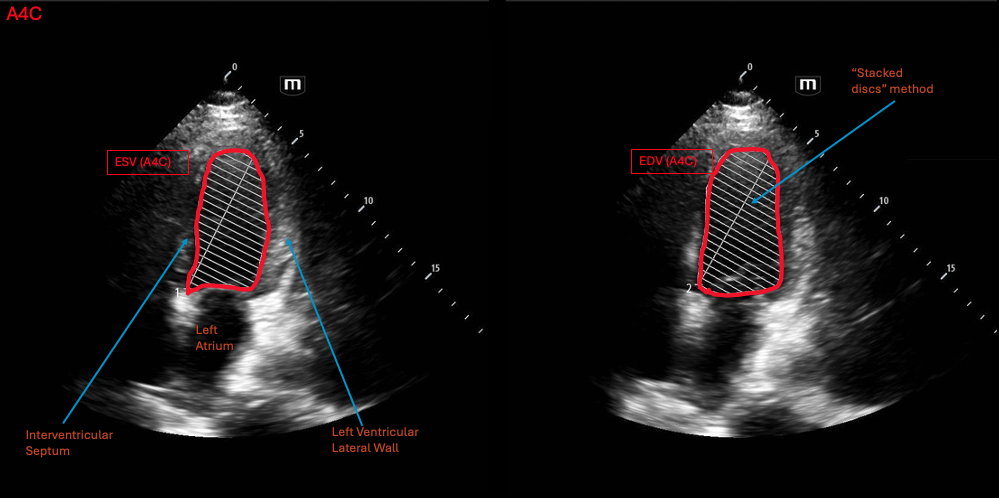

How to do

The biplane method requires two views, one in the A4C for the mediolateral measurements and another in the apical 2 chamber view (A2C) for the posteroanterior measurements of the heart. Both these planes also measure length of the LV in the base-apex axis.

Similar to FAC, the LV border is traced during end-diastole and end-systole. These tracings are taken in the A4C and A2C, resulting in a total of 4 tracings to make the final measurement. The ultrasound will take these tracings, convert them to volume measurements and utilize this to estimate an ejection fraction.

Normal values

Since the biplane method calculates volumes, the normal parameters are the normal values for LVEF. The normal range for LVEF is 55-69% and severely reduced LVEF is <30%.